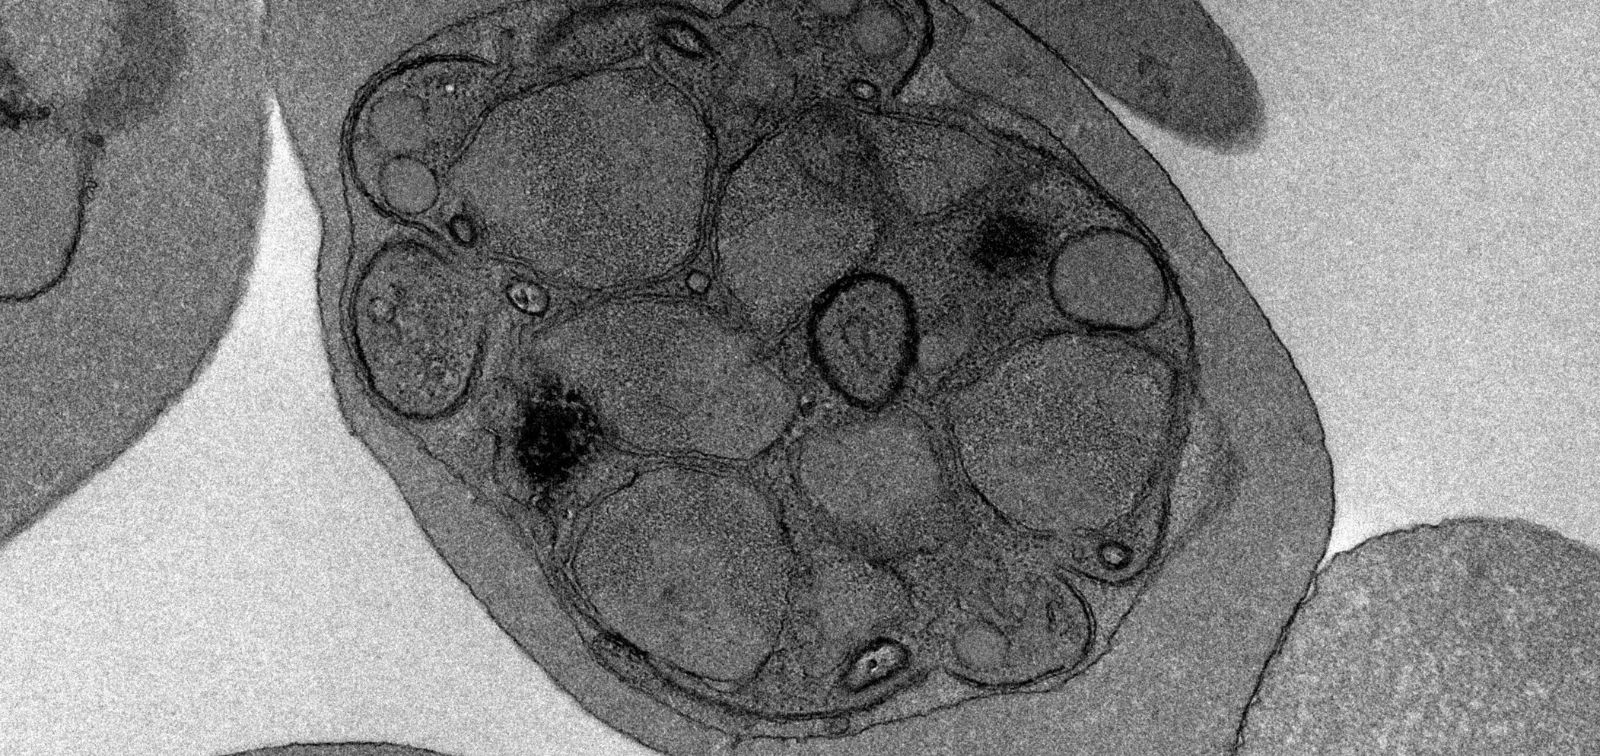

Foto: Ultrastructure of PfGNA1-disrupted parasites. Author: Maria Pia Alberiones

L’equip es va enfocar en un enzim anomenat PfGNA1, essencial per a aquesta via i estructuralment molt diferent del seu equivalent en humans. L’inactivació del gen PfGNA1 en el paràsit va provocar una pèrdua dràstica d’aquestes proteïnes d’ancoratge i una localització incorrecta de la proteïna de superfície del merozoït 1 (MSP1), que té un paper vital en la invasió dels glòbuls vermells. El desenvolupament del paràsit es va aturar en l’etapa final del seu cicle (fase de esquizont), impedint-ne la sortida dels glòbuls vermells i bloquejant així la infecció.

“Els nostres resultats confirmen el paper central d’aquesta via metabòlica per a la supervivència del paràsit i posen en relleu aquest pas enzimàtic com un punt crític de vulnerabilitat”, assenyala Maria Pía Alberione, primera autora de l’estudi. “El gran avantatge”, afegeix Izquierdo, “és que aquest enzim és molt diferent en humans: ha evolucionat de forma independent en paràsits com P. falciparum, la qual cosa ens dóna l’oportunitat de dissenyar fàrmacs que ataquin el paràsit sense afectar les cèl·lules humanes.”